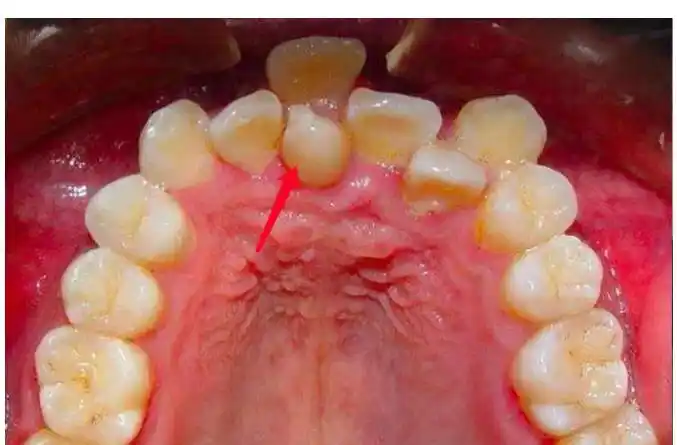

多生牙(上颚两中门牙间)supernumenary tooth (mesiodens)